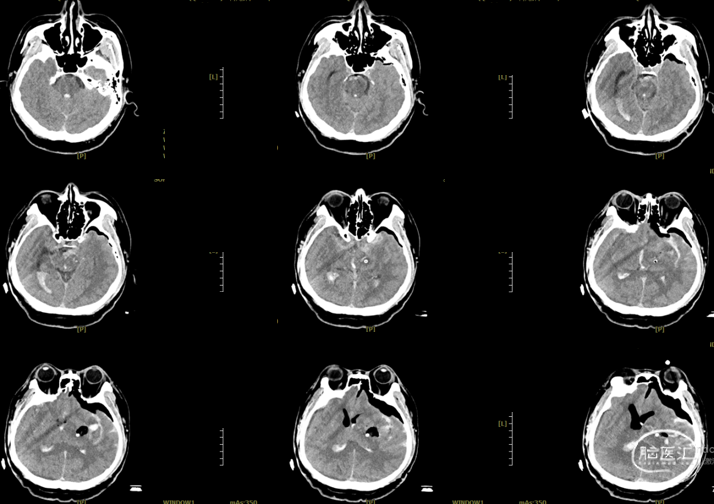

辅助检查:头胸部CT平扫2026-03-14我院脑出血并破入脑室,请结合临床复查,蛛网膜下腔出血。双肺少许纤维灶,双肺坠积性改变,请结合临床隔期复查,双肺少许小结节,考虑低危结节可能,建议结合临床年度随诊复查双肺部分小叶间隔增厚,肺水肿不除外,建议结合临床短期复查,冠脉壁钙化灶,胆囊结石。头颈部CTA2026-03-14我院颅内动脉轻度粥样硬化性改变,左侧优势型椎动脉,椎基底动脉迂曲延长。

初步诊断:1. 左侧额、岛叶、基底节脑出血破入脑室动静脉畸形?2. 脑疝;3. 高血压病3级(极高危)?4. 肺炎;5. 肺结节;6. 胆囊结石;7. 肺水肿;8. 脑动脉粥样硬化。

2026.3.14术后即刻: